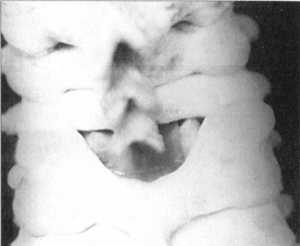

При двустороннем сцепившемся вывихе с одинаковым стоянием суставных отростков

(рис. 2.12.1-2.12.4 и рис. 2.11, графа "вывих" - вид сбоку, сзади,

сверху) признаков, характерных для ротационных смещений позвонков, нет. В эксперименте

отсутствие угловых смещений при таких вывихах выражается в исходном положении

соответствующей кривой (рис. 2.11 кривая угловых перемещений). Момент травмы,

как и при ротационных вывихах, сопровождается более значительным перемещением

позвонков по вертикали и, соответственно, более грубым воздействием на дуральный

мешок. Это выражается в глубоких всплесках кривых давления и вертикального перемещения

(рис. 2.11).

Рис. 2.12.1. Вывих. Правый сустав. Вид

сбоку |

Рис. 2.12.3. Вывих. Правый сустав. Вид

сзади |

Рис. 2.12.2. Вывих. Левый сустав. Вид

Рис. 2.12.4. Вывих. Левый сустав. Вид